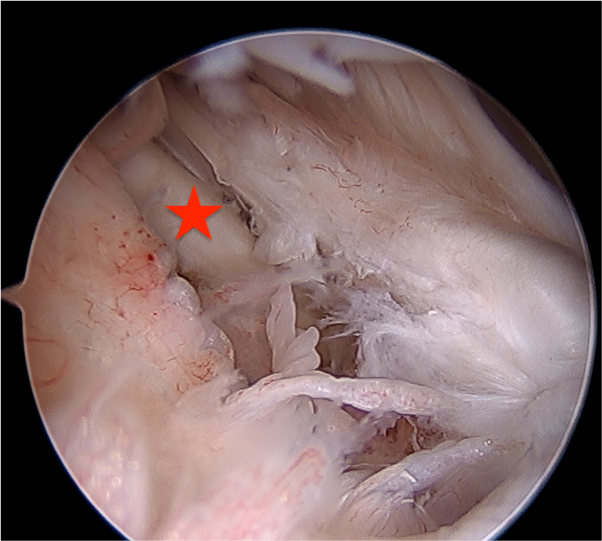

Arthroscopy

Capsule tear anteriorly, extending up into humeral insertion

Side to side repair of capsular tear

Intact anterior labrum with capsular tear, axillary nerve seen below capsular tear in axillary recess